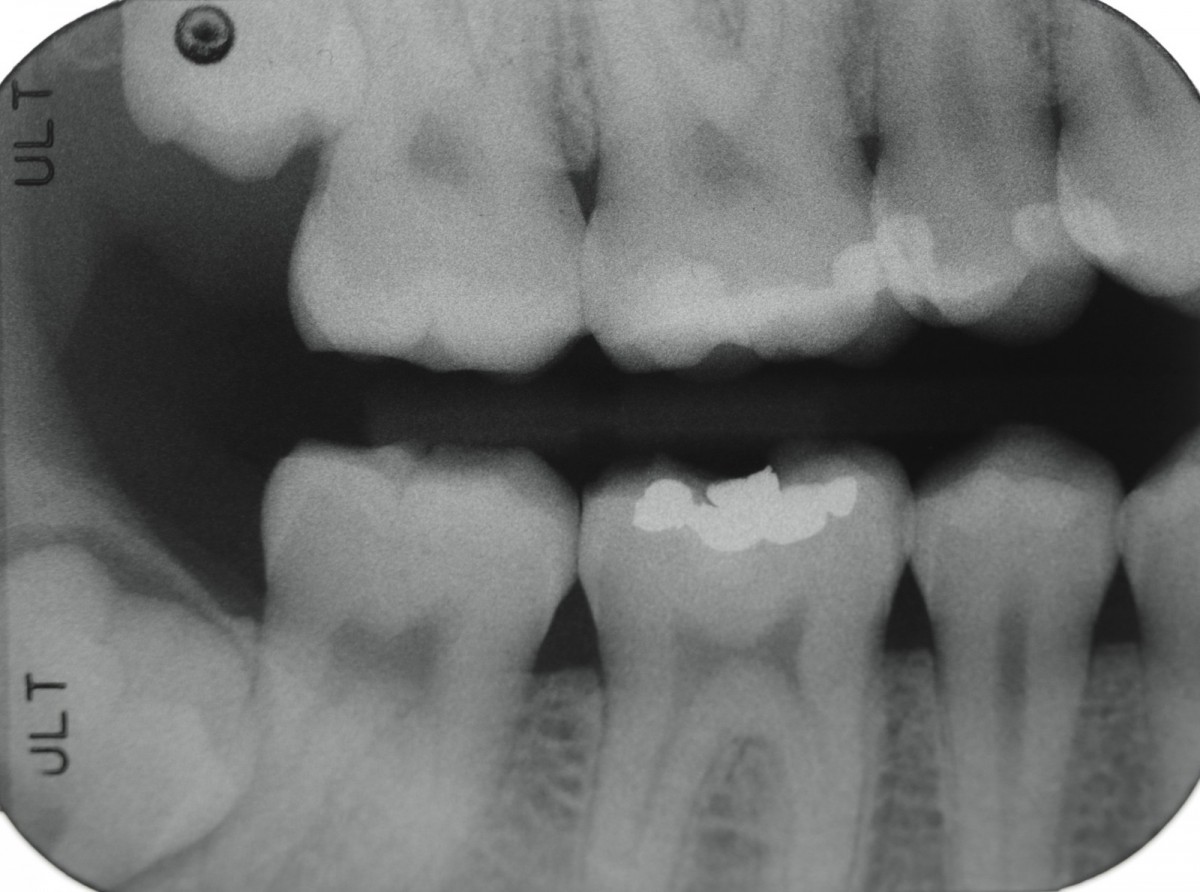

During the visit, consisting of the physical examination and instrumental examinations such as radiographs bitewings, thermal tests and compression tests (to exclude the presence of typical symptoms of a crack) at the level of the fourth quadrant, she has: amalgam restoration on dental element 4.6 associated with primary mesial caries and primary occlusal caries on 4.7.

The symptoms are not clearly identifiable by the patient but they can be traced back to dental elements 4.6 through diagnostic tests.